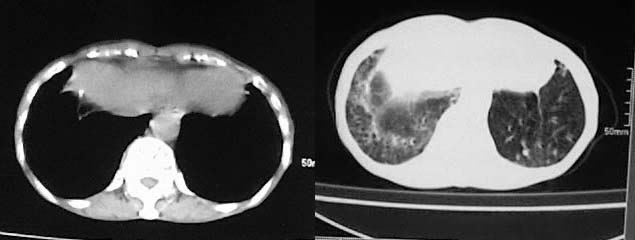

以下是引用有风的日子在2008-5-2 12:13:00的发言:[br][emb10][br][br]肺ca?有病理支持吗?[br][br]我看更象是肺tb并支扩、间质性肺炎。最好拿个病理结果来,不然这点影像资料诊断肺ca是难以服人的![br][br]至于主动脉瘤的诊断问题,国外认为≥4.0cm就可诊断了,国内对此诊断标准更为严格。患者升主动脉明显增粗,即>4cm。你诊断个升主动脉扩张并不为过!

以下是引用zjzjr在2008-5-2 14:39:00的发言:[br]支持双侧继发型肺结核,左侧胸膜肥厚,慢性支气管炎伴间质纤维化.